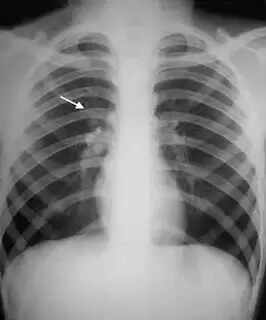

(www.kvartha.com 27.02.2016) അറബ് നാടുകളില്‍ വിസ പുതുക്കലിന്റെ ഭാഗമായി പുതിയ പരിഷ്‌കാരങ്ങള്‍.  യുഎഇ നിവാസികള്‍ക്ക് ക്ഷയമുണ്ടായിരുന്ന അവരുടെ പങ്കാളിക്കോ, കുട്ടികള്‍ക്കോ മാതാപിതാക്കള്‍ക്കോ വേണ്ടി വിസയ്ക്ക് അപേക്ഷിക്കാം. ഇതിന് മെഡിക്കല്‍ സംഘത്തിന്റെ ഔദ്യോഗിക സ്ഥിരീകരണം ഹാജരാക്കണം.

എന്നാല്‍ ക്ഷയത്തിന്റെ ലക്ഷണങ്ങള്‍ രോഗികളില്‍ ഇപ്പോഴും നിലനില്‍ക്കുന്നുണ്ടെങ്കില്‍ അവരെ നാടുകടത്താനും അധികാരമുണ്ടായിരിക്കും. നിലവില്‍ എച്ച്‌ഐവി ബാധിതര്‍ക്കാണ് വിസ പുതുക്കി നല്‍കുന്നത്.

ആദ്യമായി വിസയ്ക്ക് അപേക്ഷിക്കുന്ന ക്ഷയരോഗബാധിതര്‍ക്കോ, രോഗം ഭേദമായവര്‍ക്കോ ഈ നിയമങ്ങള്‍ ബാധകമല്ല. വീട്ടുജോലിക്കാര്‍, മുടിവെട്ടുകാര്‍, പാചകക്കാര്‍ തുടങ്ങിയ ജോലികള്‍ ചെയ്യുന്നവര്‍ വിസയ്ക്ക് അപേക്ഷിക്കുമ്പോള്‍ നിര്‍ബന്ധമായും മെഡിക്കല്‍ പരിശോധനയ്ക്ക് വിധേയമാകണമെന്നു യുഎഇ നിയമത്തില്‍ പറയുന്നുണ്ട്.

എയിഡ്‌സ്, ടിബി, ഹെപ്പറ്റൈറ്റിസ് ബി, സി, ഗര്‍ഭ പരിശോധന തുടങ്ങിയവയാണ് നിലവില്‍ നടത്തുന്ന ആരോഗ്യ പരിശോധനകള്‍. ഇവയില്‍ ഏതെങ്കിലുമൊന്നു സ്ഥിരീകരിച്ചാല്‍ യുഎഇയിലേക്ക് പ്രവേശനം നല്‍കില്ലെന്നാണ് നിയമം.

യുഎഇയില്‍ താമസക്കാരായവര്‍ക്ക് ക്ഷയമുണ്ടെന്നു കണ്ടെത്തിയാല്‍ വിസ പുതുക്കാന്‍ സാധിക്കില്ലെങ്കിലും മുന്‍പത്തെ പോലെ നാടുകടത്തില്ല. എന്നാല്‍ മെഡിക്കല്‍ സര്‍ട്ടിഫിക്കറ്റിന്റെ അടിസ്ഥാനത്തില്‍ ചികിത്സയ്ക്കായി ഒരു വര്‍ഷത്തേക്ക് വിസ അനുവദിക്കാനും നിയമമുണ്ട്.